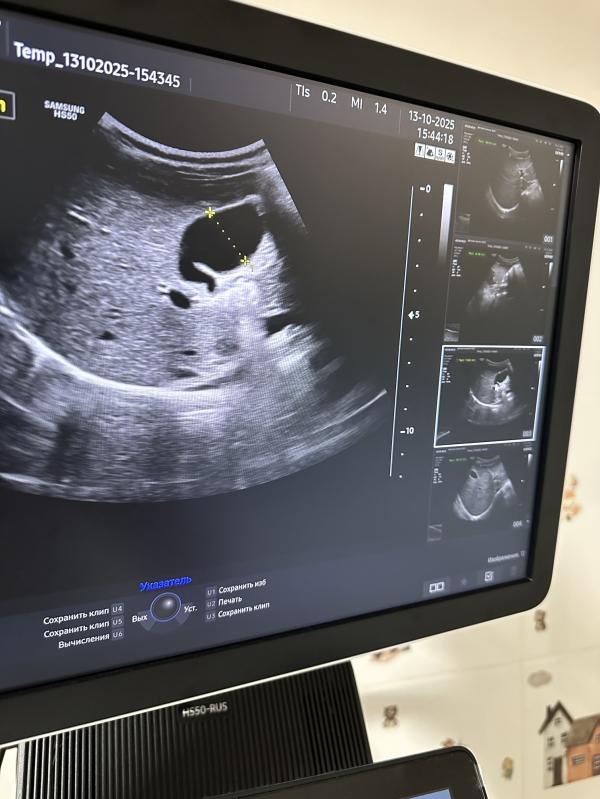

Желчный пузырь — небольшой мешочек, расположенный под печенью, предназначенный для хранения жёлчи, вырабатываемой печенью. Форма желчного пузыря обычно грушевидная, овальная или округлая. Иногда форма может меняться, приобретая перегибы, перетяжки или дополнительные складки. Такое явление называют деформацией желчного пузыря.

- Перегиб шейки желчного пузыря;

- Изгиб дна или тела пузыря;

- Формирование перегородок внутри органа.

*на сканах представлены разные желчные пузыри

Пока в просвете желчного пузыря отсутствуют признаки патологических изменений, таких как наличие желчи, конкрементов (камней) или новообразований, поводов для беспокойства нет